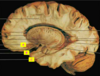

Label the arteries that supply A-C [3]

A = anterior cerebral artery (upper

and medial parts of the cortex)

(orange)

B = middle cerebral artery (lateral

areas of the frontal, parietal, and

temporal lobes) (white)

C = posterior cerebral artery (occipital

lobe and inferior parts of the

temporal lobe) (blue)